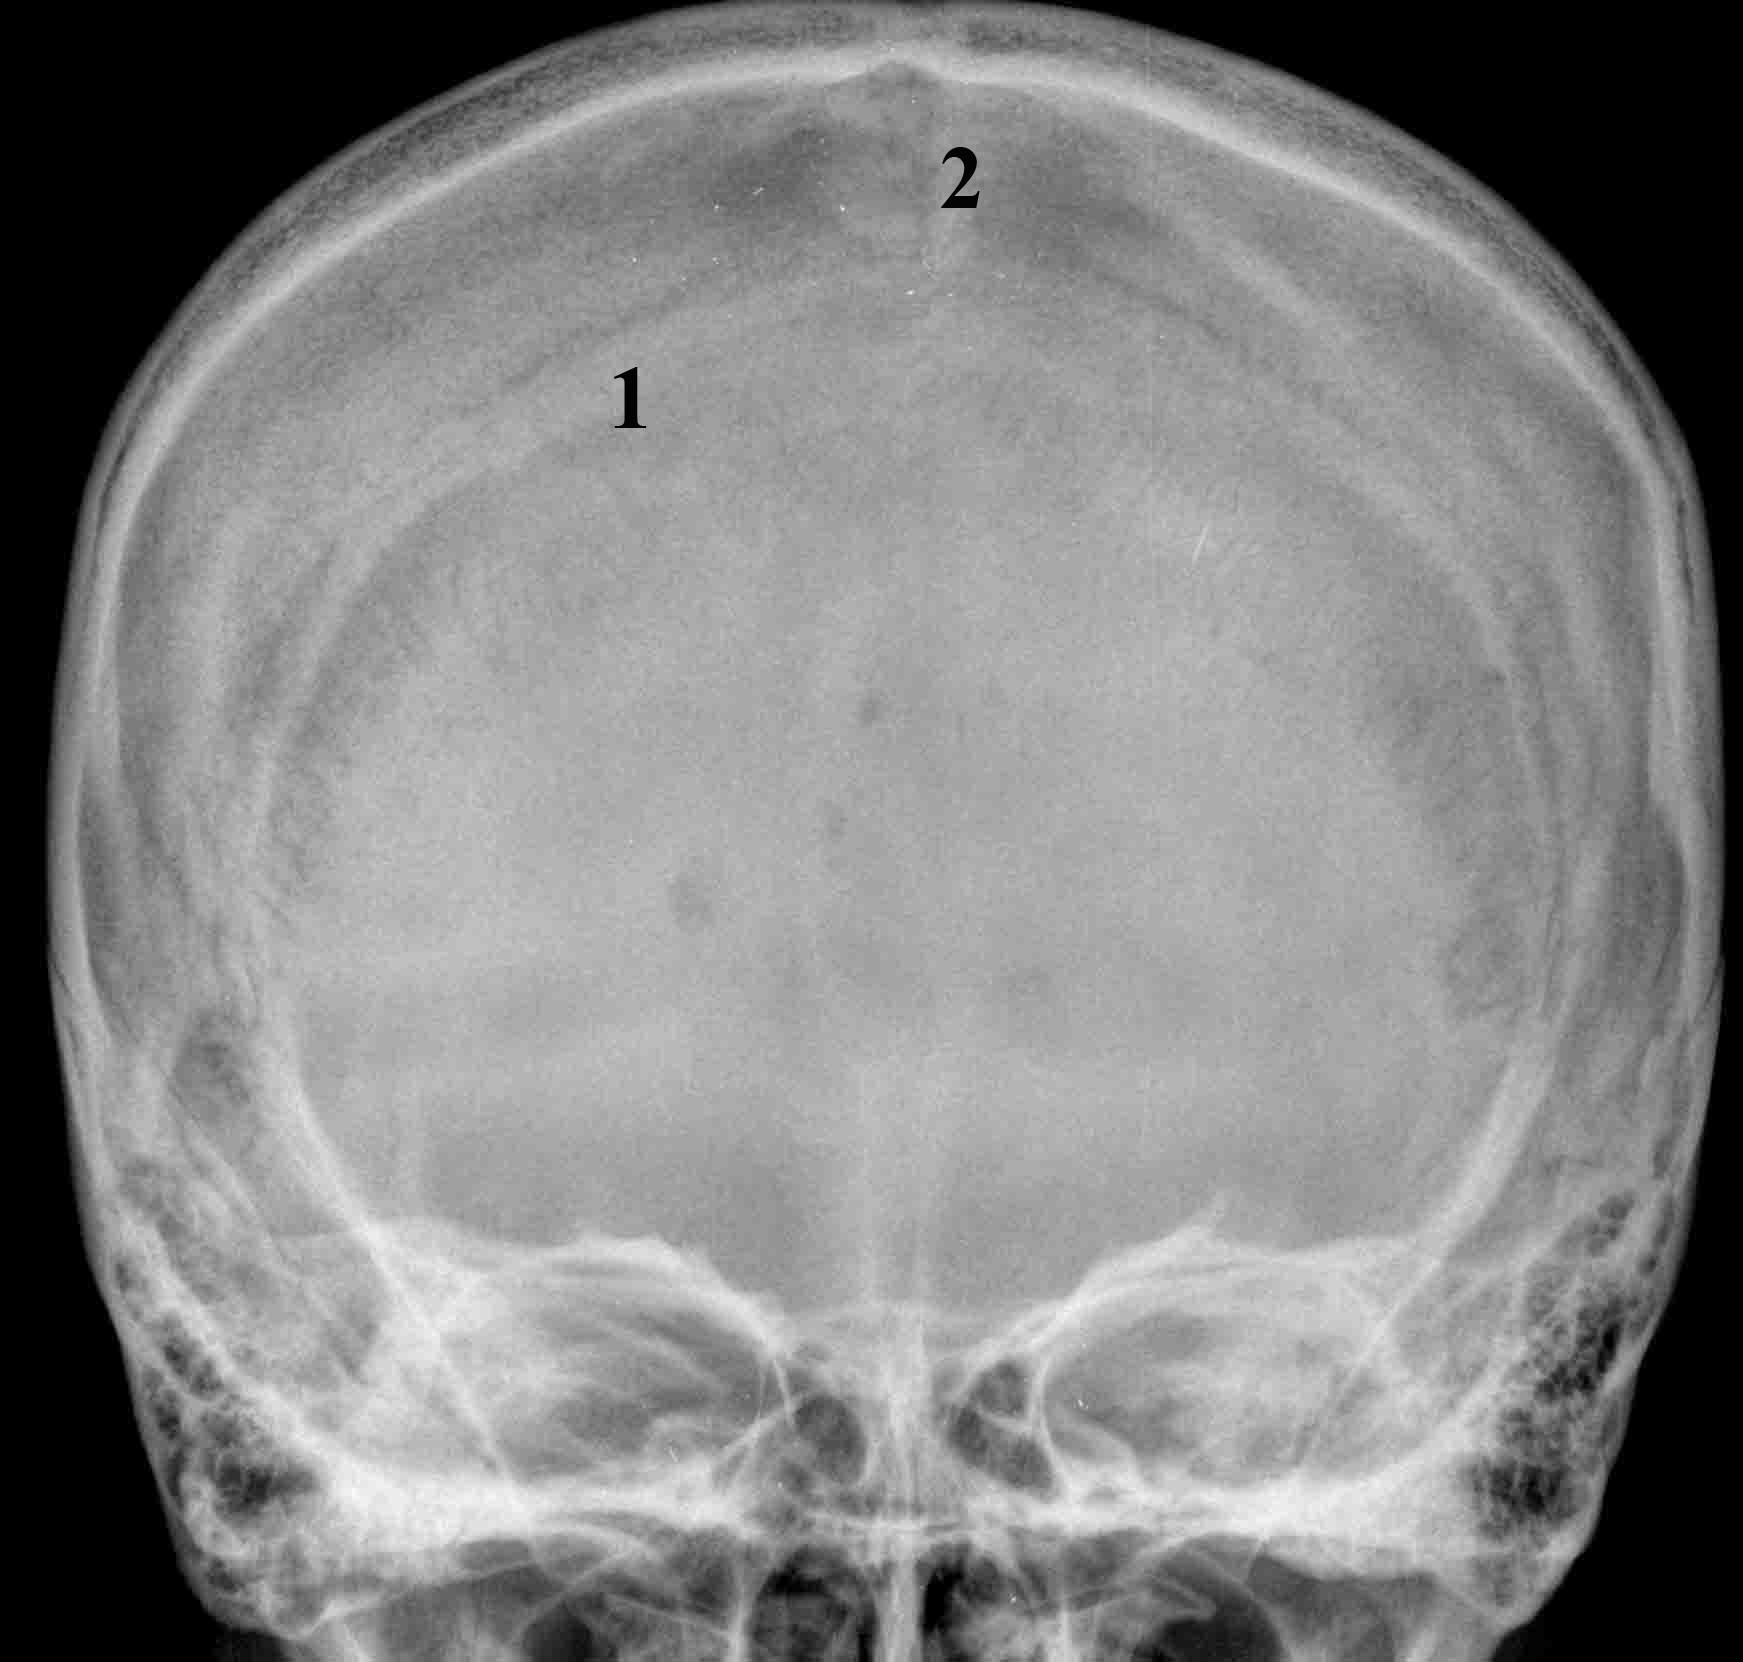

Анатомия детского черепа: Рентгеновские снимки и описание